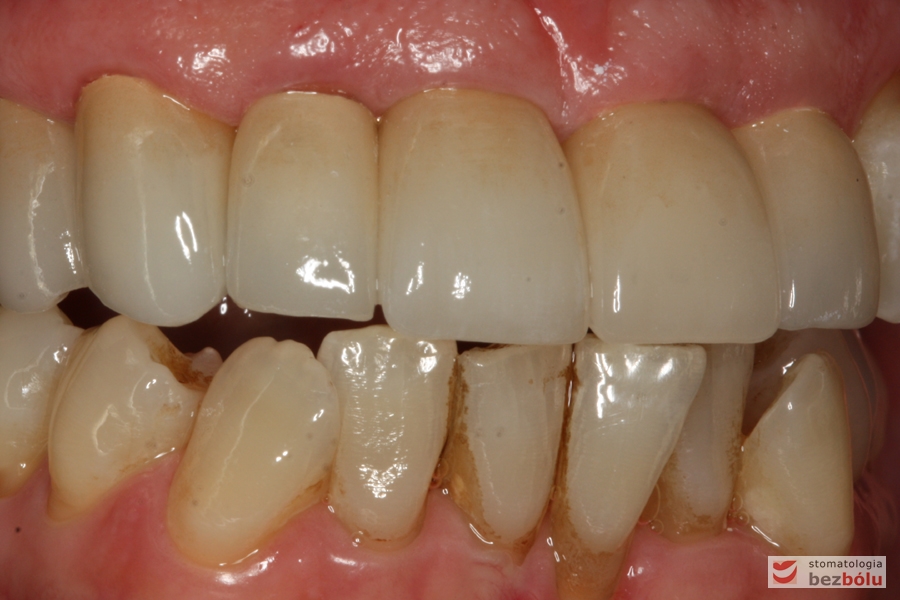

Oba łuki w zgryzie - widok frontalny, opracowane filary protetyczne na zębach własnych w szczęce

Oba łuki w zgryzie – widok frontalny, opracowane filary protetyczne na zębach własnych w szczęce